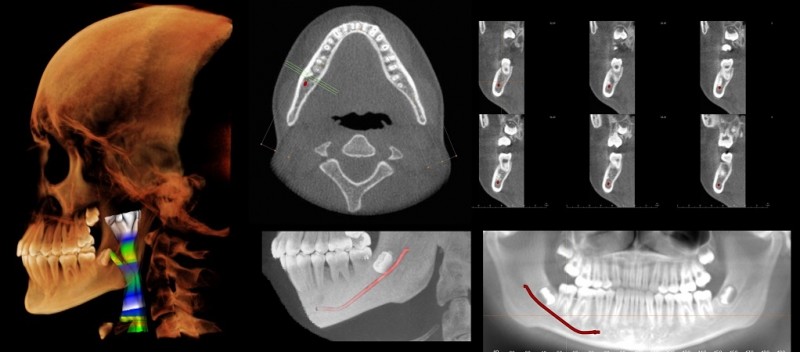

Tooth tech could help dentists diagnose problems more quickly

Imagine that your dentist's office has a new cyber assistant. This virtual aide can look for troublesome signs on your X-rays while your dentist conducts your exam. The X-ray analysis might be cheaper and more precise—and you're freed from the chair a little faster.

This scenario could become reality in the not-too-distant future, thanks to an interdisciplinary team of researchers from the School of Dental Medicine and the School of Engineering. The group is creating an artificial intelligence (AI) program that scans dental images like panoramic X-rays and alerts clinicians to results that require follow up.

"There is big potential for the use of AI in dental diagnosis," said Aruna Ramesh, professor and associate dean for academic affairs at the dental school, and a specialist in maxillofacial radiology.

Projects like this are just part of a shift toward "digital dentistry," as technology transforms a profession that was once mostly dependent on manual skills. With the aid of computers, dentists can now produce crowns in their office in about the time it takes to make a pair of eyeglasses, for example. They can also use software to design drill guides customized for their patients' jaws, to help place implants more accurately.

Imaging technologies such as MRIs and cone-beam CT scans, which produce a 3-D cross-sectional image, have expanded the ways dentists can explore beyond the teeth and gums. Panoramic X-rays, which capture the whole mouth in one two-dimensional image, are commonly used during checkups and to plan dentures, implants, braces, and extractions.

But interpreting some of these images can be time-consuming—and dental insurance typically does not cover the cost of analyzing an X-ray, Ramesh said. If digital advancements could speed up the analysis, the cost to the patient could drop.

An AI analysis can potentially cut down on human error. According to Karen Panetta, professor and dean of graduate education at the School of Engineering, images like an X-ray contain information that the eye can't detect but a computer can.

Ramesh, Panetta, and graduate engineering student Rahul Rajendran hope to teach the AI system to scan images—they are starting with panoramic X-rays—and flag areas that appear abnormal. Panetta has done similar work using AI to read mammograms or detect signs of cancer revealed by other kinds of medical imaging, as well as detecting diseases like COVID-19.

"Everybody thinks AI is a magic box you stick data in and it gives you answers," Panetta said. "But first you have to inform the AI by giving it robust data, curated by validated experts."

So Ramesh and a dental student, Ruby Wagimin, D20, have been analyzing a thousand panoramic X-rays, feeding detailed descriptions into the AI program. The program also records the researchers' spoken comments and tracks their eye movements—whether they hesitate for a fraction of a second on a particular spot, for example.

Once that data is assembled, the researchers will have the AI program spit out its assessment of the X-rays, flagging those with suspected abnormalities, and compare that analysis with the professionals' conclusions. With wide variation among normal human jaws, it is a task that's hard to standardize.

Even if the results from this initial round are promising, the AI will need years to assimilate data from hundreds of thousands more X-rays before it is ready to show up at your dentist's office—strictly in a supporting role. "The computer is not becoming the radiologist," Ramesh said. "I don't think it will ever replace a diagnostician."